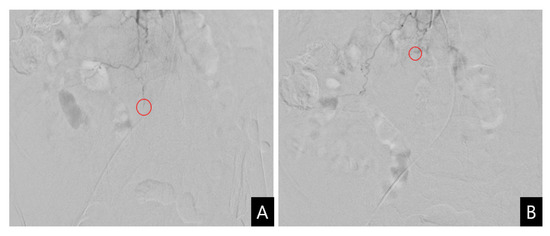

A vascular intervention specialist was consulted and urgent angiography was performed for transcatheter arterial embolization (TAE). The contrast medium was slightly extravasated from the distal fine branch of the third lumbar segmental artery, and TAE was performed at the suspected site of the leakage. Successful embolization of the bleeding vessel was performed using Gelfoam particles (absorbable porcine skin gelatin) (Figure 3). Percutaneous or surgical drainage was not considered due to the increased risk of bleeding complications and the expected potential for spontaneous reduction based on the TAE findings. The patient was treated conservatively with rest, vitamin K infusions, tranexamic acid, fresh frozen plasma, and packed RBC. During her hospital stay, her overall condition and liver function continued to improve.

Figure 3.

Transcatheter arterial embolization. (A) Selective angiography reveals the slightly extravasated contrast medium (circle) from the distal fine branch of the right third lumbar artery; (B) Embolization of the suspicious bleeding vessel is performed using Gelfoam particles (circle).